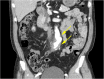

Background: Helicobacter cinaedi is rarely identified as a cause of infected aneurysms; however, the number of reported cases has been increasing over several decades, especially in Japan. We report three cases of aortic aneurysm infected by H. cinaedi that were successfully treated using meropenem plus surgical stent graft replacement or intravascular stenting. Furthermore, we performed a systematic review of the literature regarding aortic aneurysm infected by H. cinaedi.

Case presentation: We present three rare cases of infected aneurysm caused by H. cinaedi in adults. Blood and tissue cultures and 16S rRNA gene sequencing were used for diagnosis. Two patients underwent urgent surgical stent graft replacement, and the other patient underwent intravascular stenting. All three cases were treated successfully with intravenous meropenem for 4 to 6 weeks.